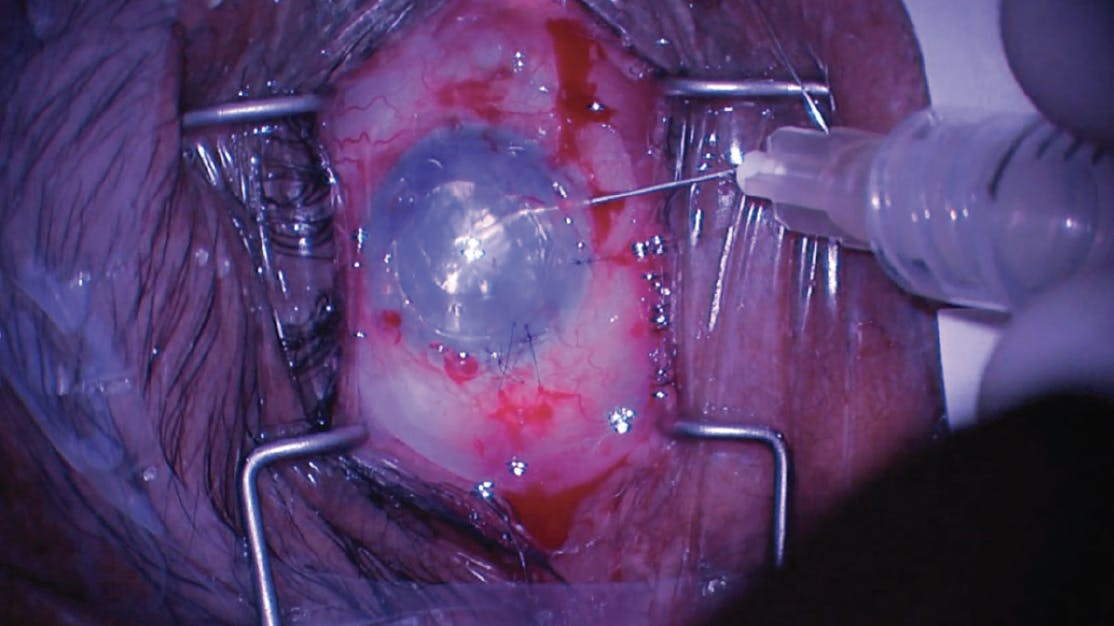

During surgery, it was noted that the failed graft was attached 360° to the iris by fibrotic tissue. In an attempt to remove it, MST retina microforceps and scissors were used to hold the graft and cut the fibrotic membrane adherences to the iris, but this maneuver was unsuccessful. Then, 23-gauge curved retina scissors were used with success to remove the fibrotic membrane adherences attaching the graft to the iris (Figure 1). An Endoserter injector (CorneaGen) was used to deploy tissue into the anterior chamber with caution, owing to significant iris atrophy. The tissue was unfolded and centralized with the help of a Sinskey hook. A 20% SF6 gas bubble was injected under the graft. The full gas bubble could not be maintained despite closing all incisions. Therefore, a 30-gauge needle was used to inject gas into the anterior chamber (Figure 2). A medium-sized gas bubble was held inside the anterior chamber, and IOP was within normal range.

<p>Figure 2. A 30-gauge needle was used to inject gas into the anterior chamber.</p>

Figure 2. A 30-gauge needle was used to inject gas into the anterior chamber.